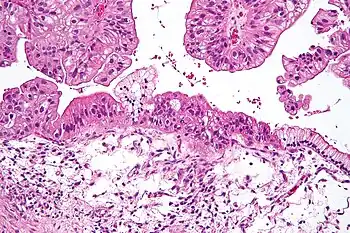

![]() | |

| Micrograph of a mucinous ovarian carcinoma stained by H&E | |